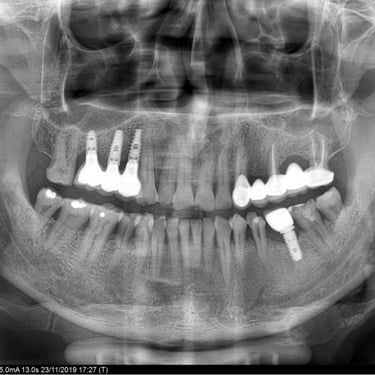

Implant restorations